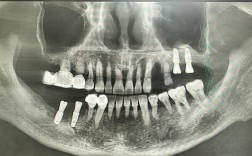

- 这是最初的步骤,医生会进行口腔检查,拍摄口腔全景片(X光片)、CT扫描(锥形束CT),评估你的牙槽骨条件(高度、宽度、密度)、邻牙情况、咬合关系等。

(图片来源网络,侵删)- 检查评估:1-2周